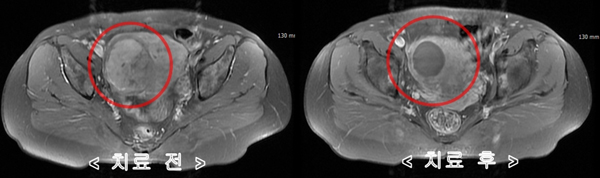

자궁에 발생하는 질환 중 대표적으로 알려진 것은 자궁근종과 자궁선근증, 다낭포성난소증후군 등인데 젊은 임신기 여성은 물론 중년 여성까지 연령에 상관없이 발생하고 있으며 그 중에서도 35세 이상 여성에게서 40~45% 정도가 겪고 있을 정도로 흔한 질환이 자궁근종이었습니다.발생한 위치에 따라 증상이 다르지만 경우에 따라서는 통증과 부정출혈을 동반할 수 있어 불임, 난임, 유산에 영향을 미치므로 임신 중인 여성이라면 반드시 정기적으로 자궁검진을 실시하여 예방과 적절한 치료가 이루어지도록 하는 것이 중요했습니다.자궁근종 하이프 시술은 자궁질환을 치료하는 가장 효율적인 방법으로 알려져 있으며 자궁선근증에도 활용되고 있었습니다.발생 위치에 따른 구분자궁근종은 자궁근육층에 근종이 발생한 것으로, 1cm 미만 크기부터 12cm 이상의 거대 근종까지 다양하게 확인됐습니다.개수나 위치에 따라 증상이 다르고 적절한 치료시기와 방법이 다르기 때문에 진단을 받는 과정에서 의료진의 숙련도와 임상경험 유무 및 검사장비와 치료장비 등 의료적 환경이 적절하게 갖춰져 있는지 확인하는 것이 중요했습니다.근층내근종가장 흔하게 발생하는 자궁근종으로 근육 중간 부위에 근종이 발생하여 자궁을 비대화시키고 내막을 확장시켜 복부압박감과 부정출혈 및 평소보다 많은 생리를 유발하였습니다. 장막하근종자궁 바깥쪽에 위치한 장막층에서 발생한 것으로 근종이 커지고 하복부에 대한 불쾌감이 심해져 근층 내 근종 다음으로 많이 발생했습니다.하복부가 볼록하게 돌출되어 빈뇨감과 잔뇨감을 느끼거나 배뇨 및 배변 장애를 겪는 경우가 자주 있었습니다. 점막하근종자궁 내 점막에서 발생하는 근종으로 크기에 관계없이 출혈이나 심한 생리통을 유발하고 임신에도 영향을 미치게 되었습니다.잦은 출혈로 빈혈을 일으키고 자궁 내부에 위치하기 때문에 불임은 물론 유산이나 조산에 결정적인 요인이 되는 경우가 많아 즉시 치료가 필요했습니다.자궁근종이 의심되는 증상발생 위치와 개수 및 크기에 따라 치료 여부가 달라졌고 자궁 건강에 미치는 영향도 모두 달랐습니다.하지만 자신의 몸에 있어서는 안 되는 비정상적인 조직인 것만은 변하지 않기 때문에 의심 증상을 알아두고 체크해서 조기 치료를 할 수 있도록 하는 것이 무엇보다 중요했습니다.생리통이 항상 심하게 느껴졌어요.생리 전 하복부 통증과 골반 안쪽 통증이 심했습니다.생리 중에 출혈량이 많았어요.생리 중 빈혈 증상을 경험했어요.부정출혈을 자주 경험했어요.아랫배가 중후해서 통증과 압박감을 잘 느꼈어요.아랫배가 나와서 가스가 잘 찼어요.잔뇨감과 빈뇨감으로 불편함을 느꼈습니다.아랫배와 복부에 단단한 막대기가 닿았어요.자궁근종 치료법근종의 종류나 임신력 등을 고려해서 치료 방법을 선택하는데 수술적인 치료인 복강경과 비수술적인 치료인 자궁내시경과 자궁근종 용해술 그리고 하프 시술이 있었습니다. 이 중 자궁근종 하이프 시술은 체력적 부담을 줄임과 동시에 자궁을 보존할 수 있는 방법으로 대중적인 인기를 얻고 있으며 자궁 손상을 피하고 자궁이나 임신력을 보존하는 데 최적화된 방법이라고 할 수 있습니다.하이푸는 고강도 집속 초음파 장비는 JC200D를 사용하는데, 다만 자궁근종과 자궁선근증 치료를 목적으로 개발된 장비였습니다. 고강도 집속 초음파가 복부를 투과해 근종만을 찾아 고온에서 괴사를 유도함으로써 실시간 모니터링과 1.1mm 미세초점으로 움직이면서 타겟팅할 수 있어 근종의 위치와 크기에 관계없이 정확하게 치료할 수 있었습니다.비용이 아닌 결과가 중요한 치료여성에게 자주 발생하는 자궁근종이지만 제대로 치료하지 않으면 재발이 잦아 임신이나 출산에 악영향을 미칠 수 있었습니다. 따라서 비용적인 부분을 보기 전에 다양한 임상 경험을 가진 의료진이 진료를 책임지고 있는지 자궁을 살릴 수 있는 하이프를 우선시하는지 먼저 알아보는 것이 좋았습니다.레아산부인과에서는 병변 위치를 명확히 확인할 수 있도록 시술 전후 2회에 걸쳐 MRI 촬영을 실시하였으며, 산부인과 전문의이자 가톨릭대학교 외래교수인 이경숙 원장이 직접 진료하고 있는 만큼 1:1 맞춤 치료로 건강한 생활과 건강한 신체를 유지하기 위해 필요한 지원을 받을 수 있었습니다.여성에게 자주 발생하는 자궁근종이지만 제대로 치료하지 않으면 재발이 잦아 임신이나 출산에 악영향을 미칠 수 있었습니다. 따라서 비용적인 부분을 보기 전에 다양한 임상 경험을 가진 의료진이 진료를 책임지고 있는지 자궁을 살릴 수 있는 하이프를 우선시하는지 먼저 알아보는 것이 좋았습니다.레아산부인과에서는 병변 위치를 명확히 확인할 수 있도록 시술 전후 2회에 걸쳐 MRI 촬영을 실시하였으며, 산부인과 전문의이자 가톨릭대학교 외래교수인 이경숙 원장이 직접 진료하고 있는 만큼 1:1 맞춤 치료로 건강한 생활과 건강한 신체를 유지하기 위해 필요한 지원을 받을 수 있었습니다.희아산부인과의원 서울특별시 강남구 강남대로 340 4층희아산부인과의원 서울특별시 강남구 강남대로 340 4층희아산부인과의원 서울특별시 강남구 강남대로 340 4층희아산부인과의원 서울특별시 강남구 강남대로 340 4층희아산부인과의원 서울특별시 강남구 강남대로 340 4층희아산부인과의원 서울특별시 강남구 강남대로 340 4층